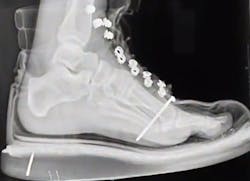

The first time he nailed through bone came while shooting sole plates into the subfloor. He ran out of hose, so he gave it a yank. That pulled his hand down, pushing the gun tip into his boot. The result was a nail through the foot – the picture above is the x-ray he got in the emergency room before they yanked the nail. He lost a month of work.